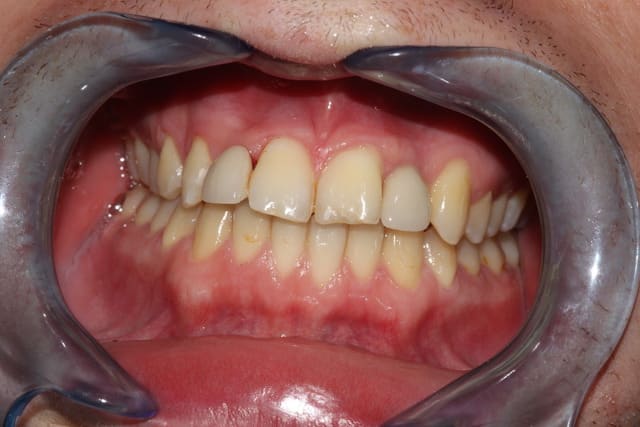

Patiente de 44 ans, sympathique et facile à soigner, fumeuse (1 demi paquet/jour mais ne peut pas s'en passer), pas de problème de santé, coagulation rapide de ce que j'ai pu voir après l'avulsion. Au niveau oral, on est dans un contexte de séquelles de maladie paro importantes: nombreuses mobilités et récessions gingivales, quelques poches limités, mais pas d'inflammation ni infection.

Grande confiance dans le dentiste, préférant le confort à l'esthétique (elle envisageait de repartir sans sa 21 avant que je lui dise que je pouvais le gérer avec la dent avulsée), possède des édentements encastrés postérieurs mandibulaires qu'elle ne compte pas remplacer (aspect financier).

Bref, son soucis est de ne plus avoir de douleurs ni de dents mobiles, à moindre cout. Je doute d'arriver à la motiver pour l'implant, mais je vais essayer d'au moins l'envoyer consulter (je ne pose pas d'implants moi même).

Comme je l'ai dit, la 21 ne lui pose pas plus problème que çà ("Le ridicule ne tue pas" m'a-t-elle dit en envisageant le cas où elle aurait du rester un moment sans sa 21).

Je suis parti sur le bridge collé composite de canine a canine. Je vous dirait ce que çà donne. J'ai également parlé de l'implant à terme qui pourrait se tenter aussi.